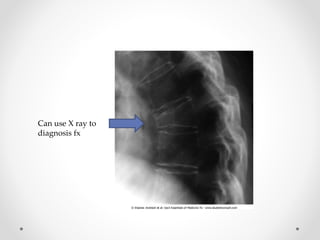

Can use X ray to

diagnosis fx

Vertebral Fracture • 2/3are silent – minimal or no trauma • 20-30% are multiple • 2/3 are painless • May cause pleuritic-type pain (pain with each breath) • 4cm loss of height should raise suspicion Wedge fracture Compression fracture L1 and L3 Burst fracture

Can use Xray to diagnosis fx

• #62 Deformity may take days to weeks to develop so serial plain films may be necessary An incident vertebral fracture increases risk of subsequent fracture 5-7x Thoracic fractures can restrict lung function and cause problems with digestion